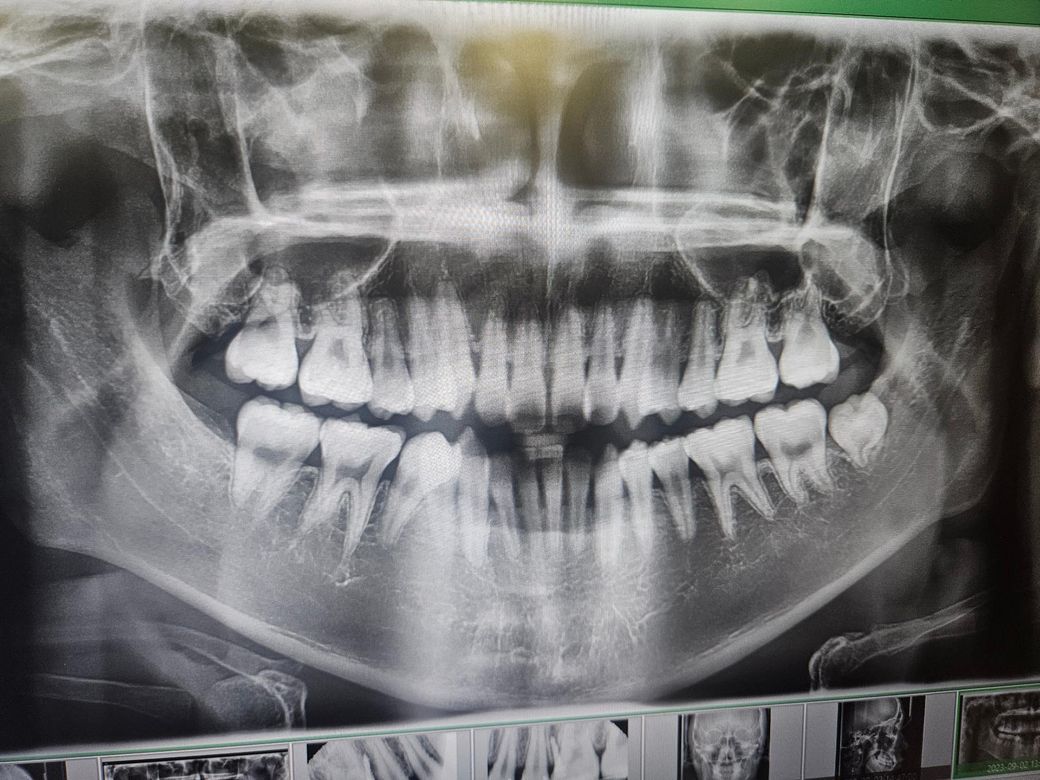

첫번째가 교정 시작할 때, 두번째가 현재입니다.

• 1번 째 사진